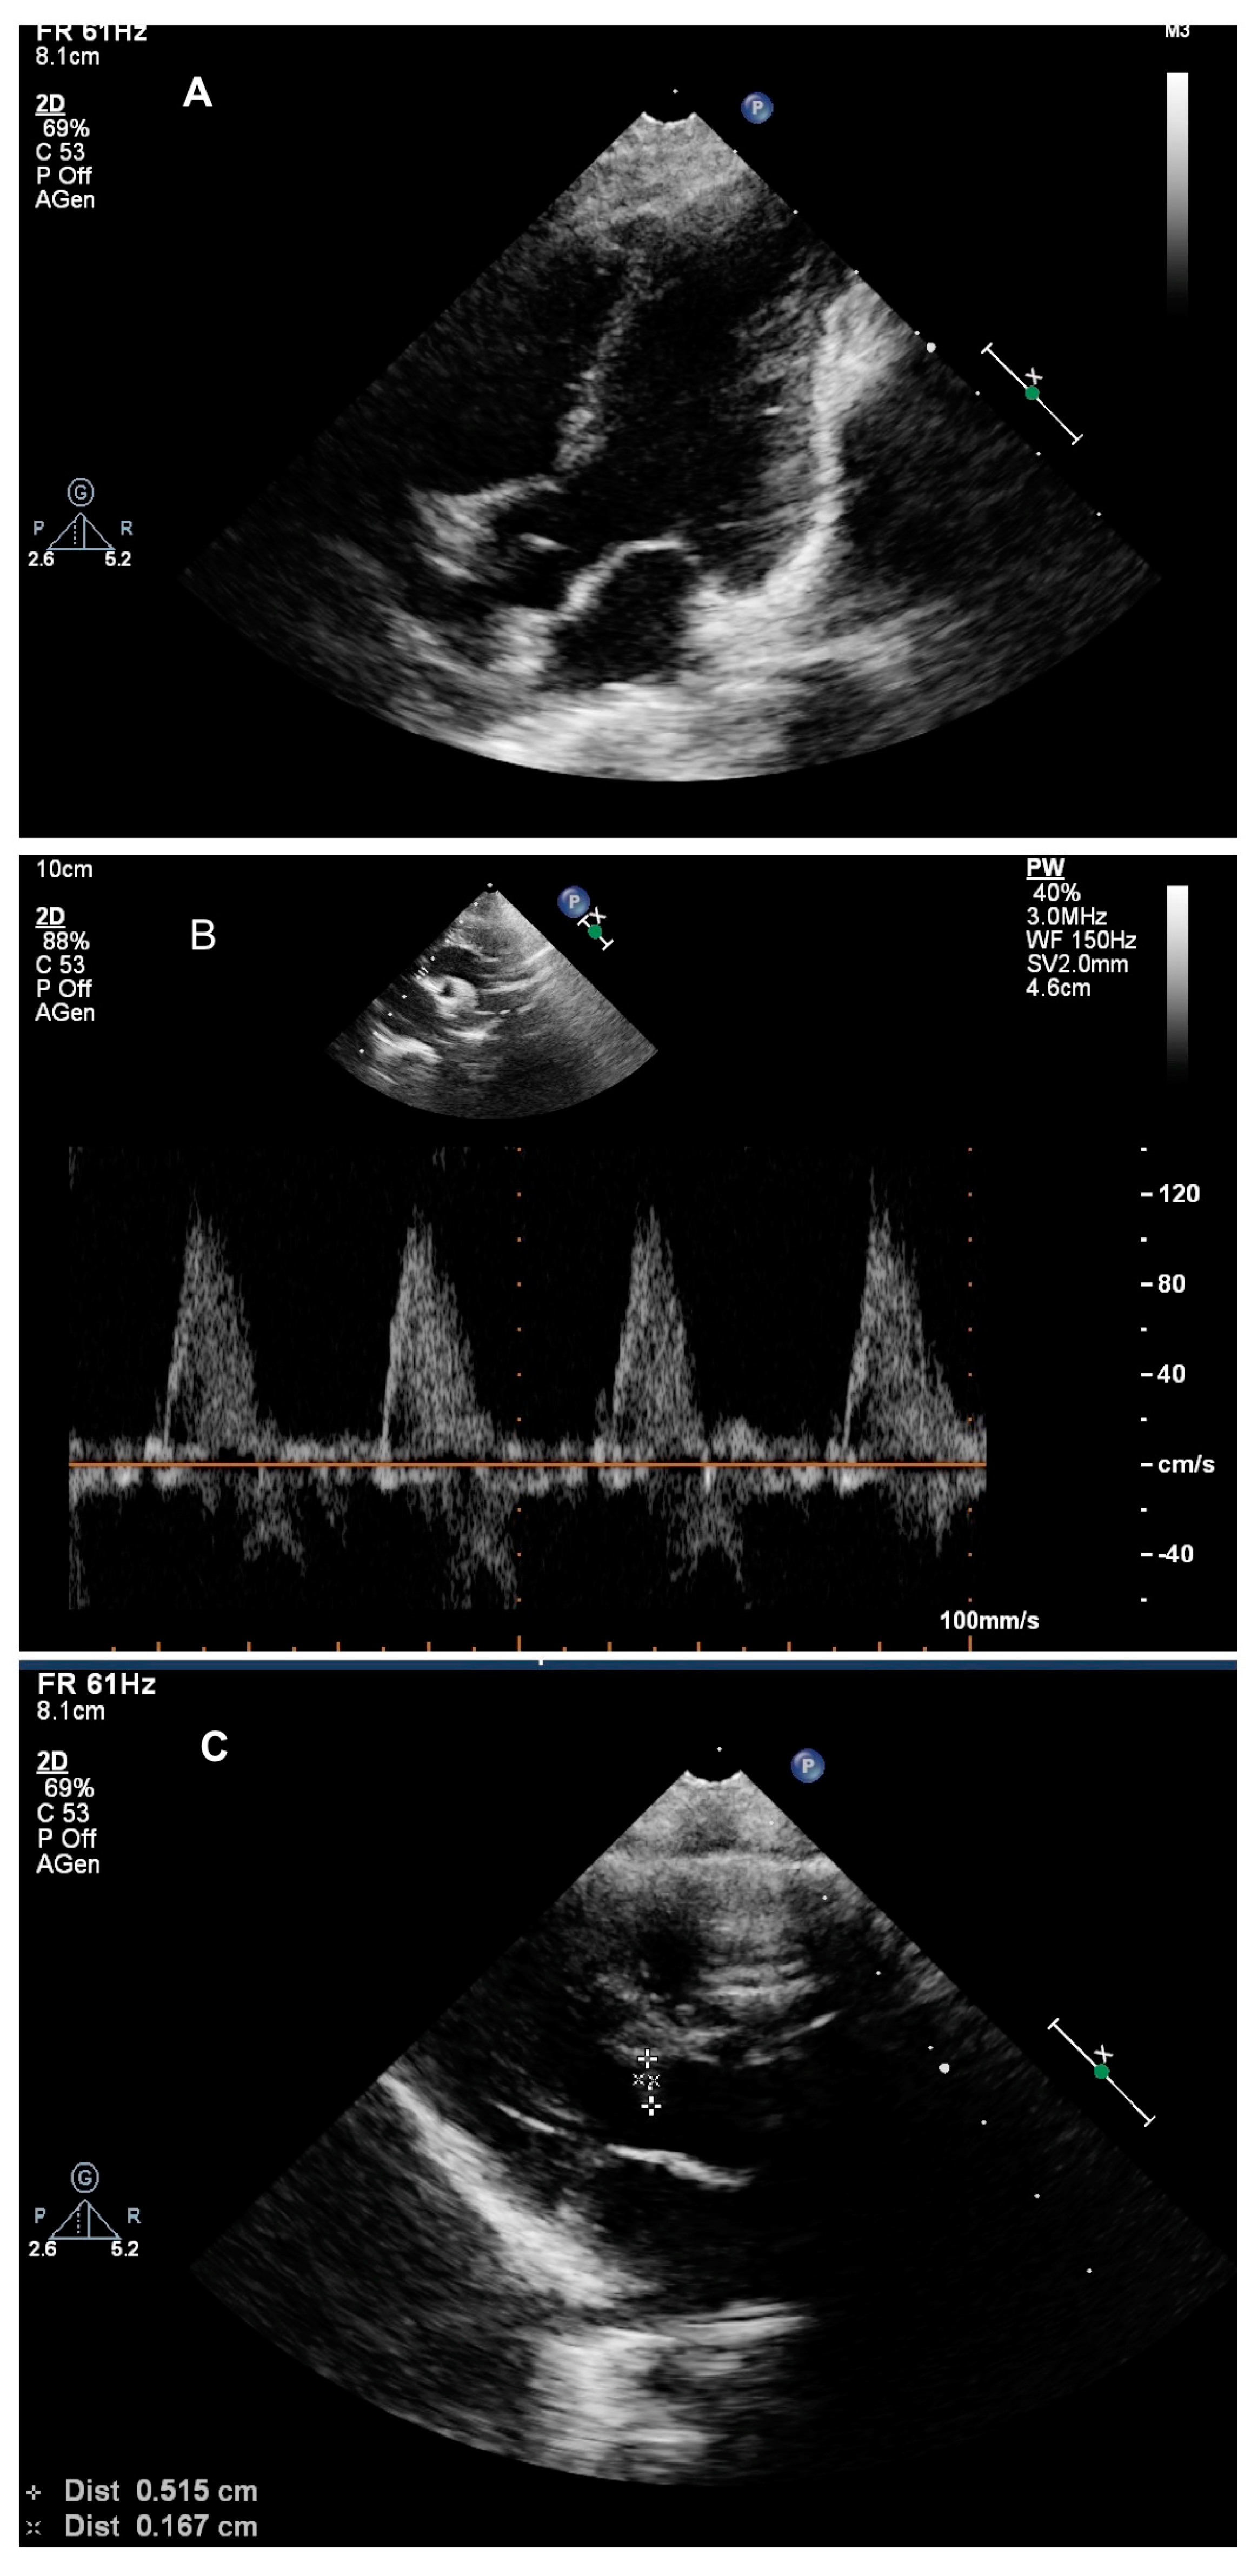

2. Case Presentation